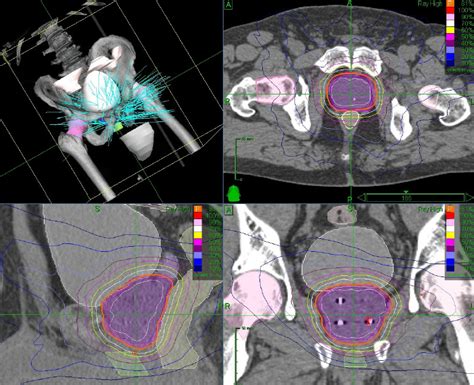

836×538

Weebly

Radiation Therapy Techniques for Treatment of the Prostate - Karen ...

565×397

Radiation Therapy Techniques for Treatment of the Prostate - Kare…